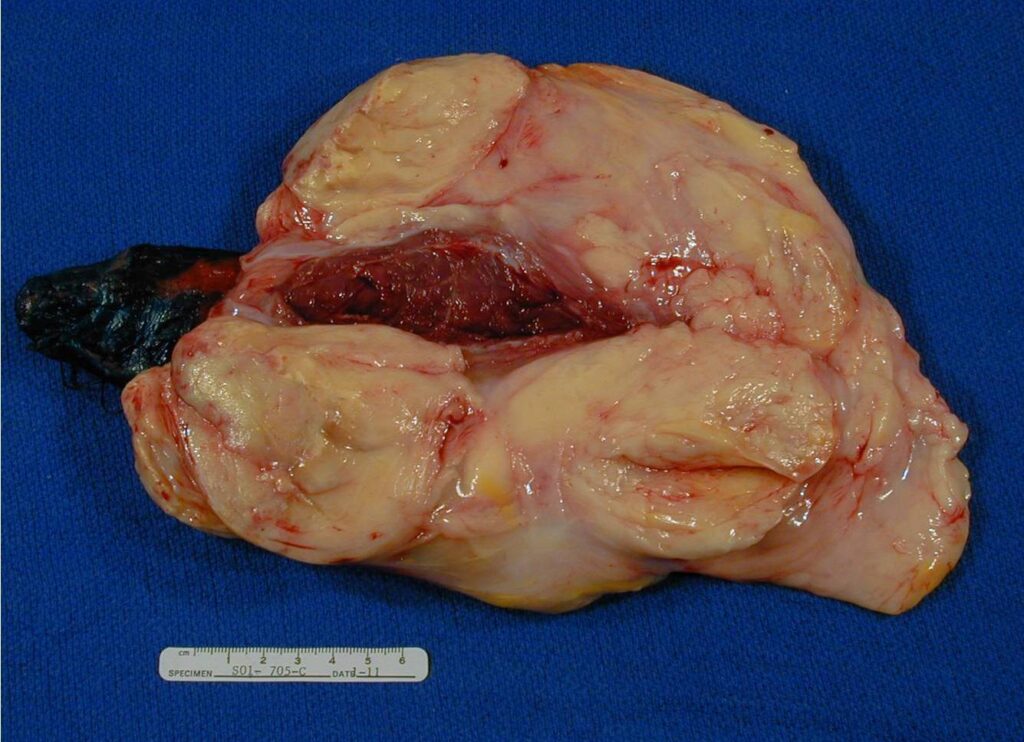

PATHOLOGY

Multinodular growth within and between skeletal muscle

• Soft and pale yellow on cut